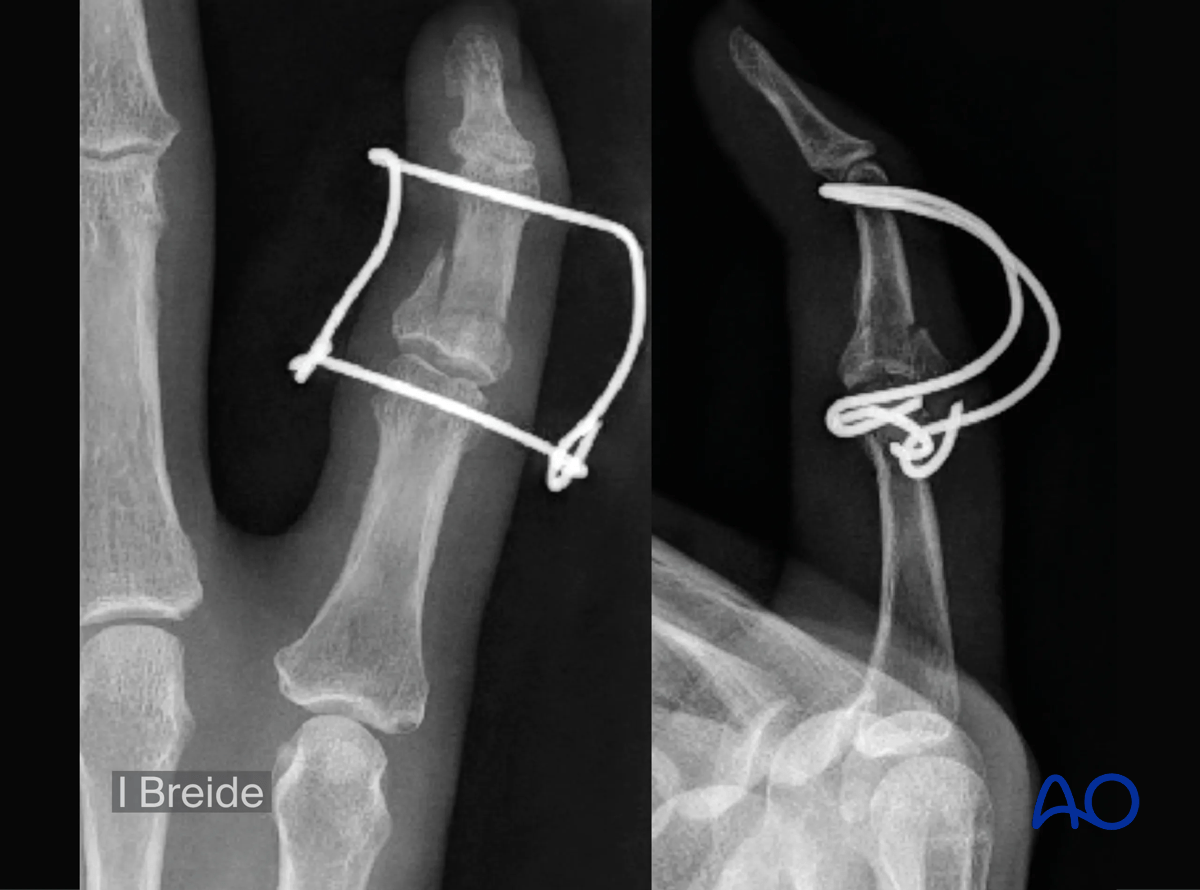

Stabilization with a parabolic (Fibonacci type) dynamic external fixator